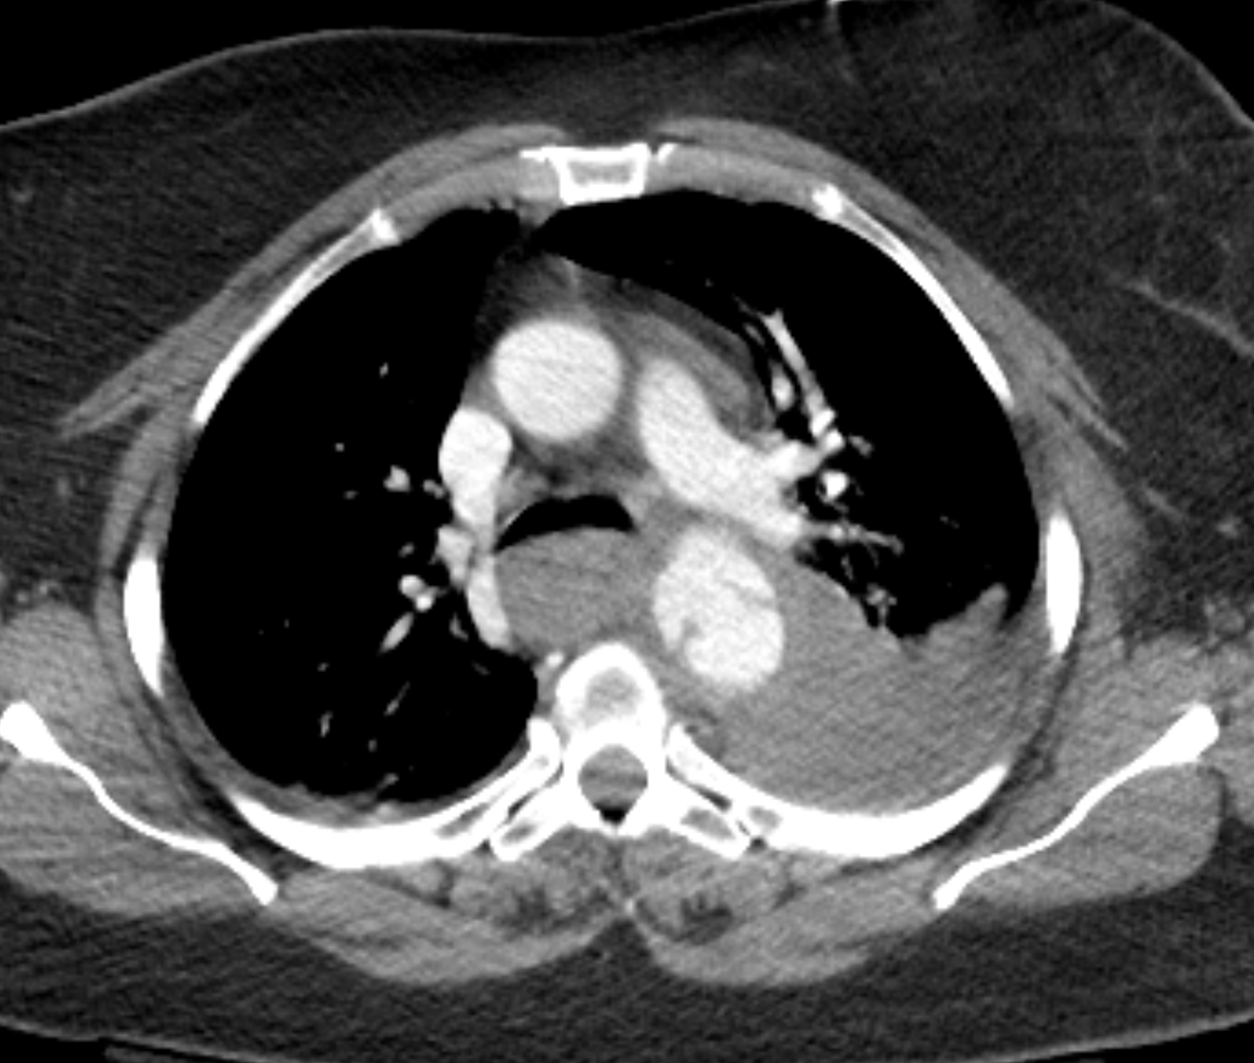

Age: 68

Sex: Female

Indication: Trauma

Sample ReportMild widening of the superior mediastinum with poor definition of the aortic arch, which raises concern for traumatic aortic injury. Recommend correlation with chest CTA.

Hazy opacification throughout the left hemithorax, which likely represents a combination of layering pleural fluid and airspace opacification related to atelectasis, contusion, and/or aspiration.